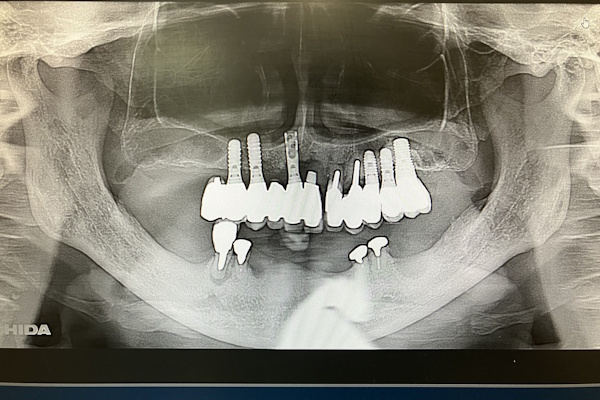

レントゲン画像